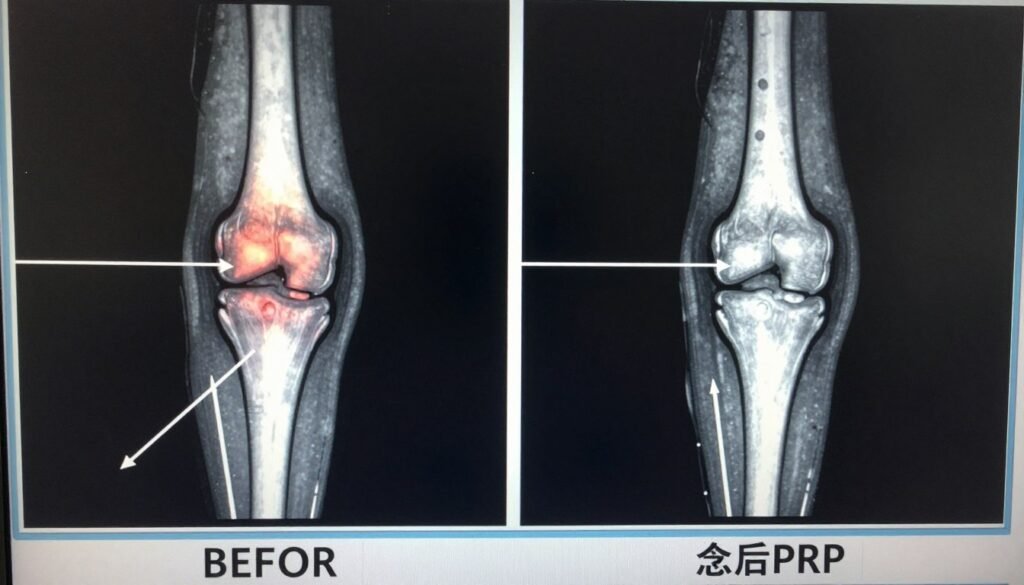

Advanced Platelet-Rich Plasma (PRP) Protocols: 2025 Refinements

Platelet-Rich Plasma (PRP) therapy has evolved significantly in 2025, with new protocols that enhance its effectiveness for knee pain. This newest treatment for knee pain 2025 approach uses your body’s own healing factors to reduce inflammation and potentially stimulate cartilage repair.

2025 PRP Advancements

The latest PRP protocols utilize precise concentration techniques and personalized formulations based on the patient’s specific condition. Ultrasound-guided injections ensure accurate placement within the knee joint, while combination approaches with hyaluronic acid have shown enhanced results in recent studies.